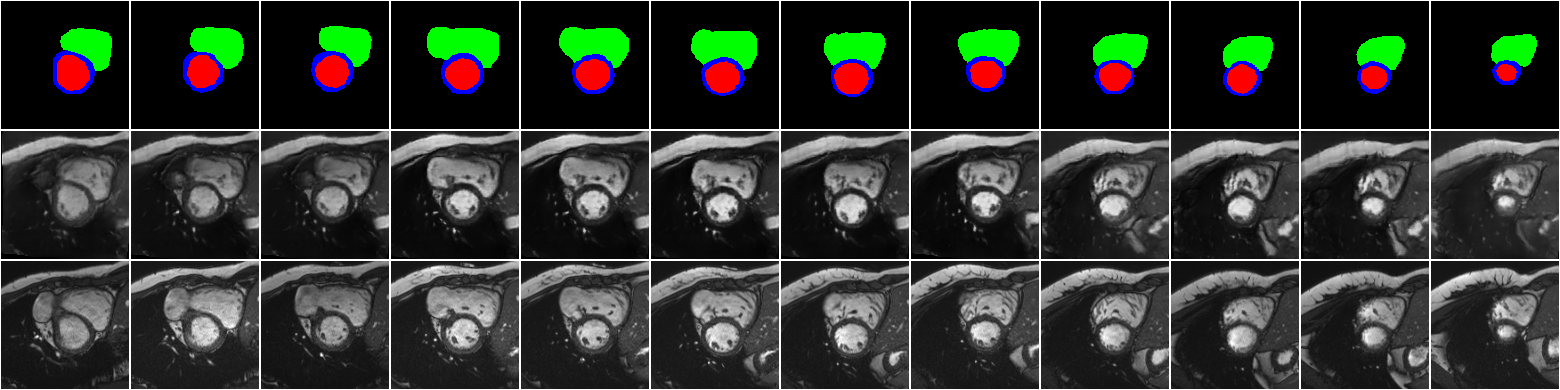

First, we show the synthetic images when using the labels of the ACDC dataset as inputs of SPADE GAN. Figure LABEL:fig:synth_slice_ED shows different synthetic slices (from apex to base) for one subject of the ACDC dataset in the end-diastolic phase. Similar results for the end-systolic phase are depicted in A, \figurereffig:synth_slice_ES. As seen in these figures, the synthetic images are coherent between slices even though the training is done on 2D slices. Moreover, the three classes of interest in the heart have been reconstructed reasonably well. There are some differences between the background tissues in real and synthetic images. This is because all different tissues in that region are mapped into one class in the label map (background shown by black in the label map). Thus the SPADE GAN is not able to preserve their spatial information.

fig:synth_slice_ED

This section includes additional synthetic images. \figurereffig:synth_slice_ES includes synthetic slices for the fixed end-systolic phase for one patient of the ACDC dataset.

fig:synth_slice_ES